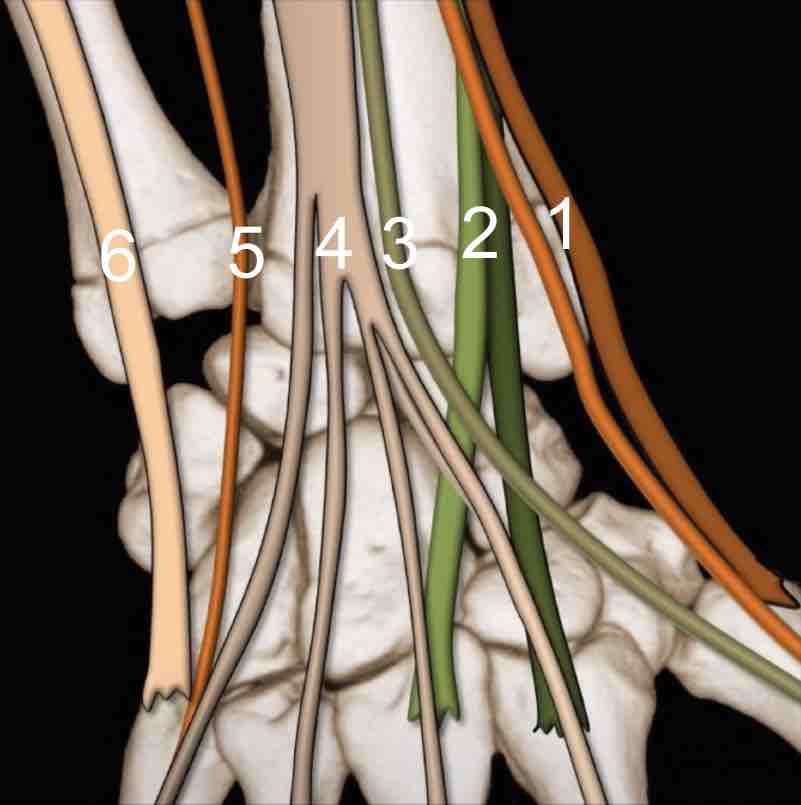

Pas d'épanchement dans les articulations radiocarpienne, radioulnaire distale et médiocarpienne.

Pas d'anomalie décelable des tendons extenseurs et fléchisseurs.

De Quervain

Epaississement rétinaculaire supérieur à 1 mm autour du premier compartiment des extenseurs.

Aspect hypoéchogène. Hyperhémie associée. Douleurs reproduites au passage de la sonde.

Pas d'anomalie des tendons du court extenseur et du long abducteur du pouce.

Pas d'éperon osseux ni de septum intertendineux.

sd canal carpien = nerf > 12-15 mm², index d'aplatissement > 3,

sd canal carpien = nerf > 12-15 mm², index d'aplatissement > 3,nerf hypo +/- signal Doppler, bombement rétinaculum > 4 mm,